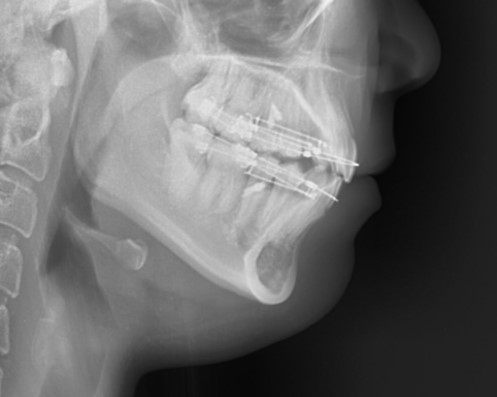

3) 엑스레이 비교

▶ 치열 후방 이동량 확인

▶ 상·하악 치열과 골격 관계가 더 조화롭게 정리된 모습

▶ 교합 안정성 및 치근 상태 확인